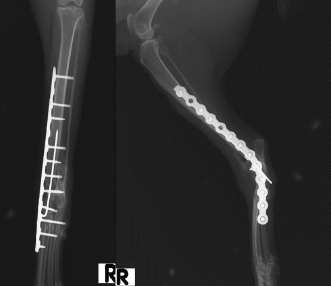

An 18-month-old female stray European cat was referred to the Veterinary Teaching Hospital of the University of Camerino, Italy. Anamnestic data reported a distal tibial epiphyseal sliding fracture (SH1) of the right hind limb inadequately treated 8 months prior with an intramedullary pin by colleagues and consequent chronic tarsocrural instability. Gait evaluation showed a non-weight bearing lameness (grade 4/5) of the right hind limb. An orthopedic examination revealed severe pain during the manipulation of the right tarsus, with bone crackling during stressed manipulation elicited by tibiotarsal joint laxity. Mediolateral and craniocaudal projections of the right tarsus showed failure of the fracture implant (intramedullary pin) caused by an inadequate choice of the apparatus and an incorrect osteosynthesis technique, with a caudomedial displacement of the right distal tibial epiphysis and a moderate process of bone remodeling and resorption (Fig. 1). The patient underwent pantarsal arthrodesis for the recovery of limb functionality. The anesthetic protocol included premedication with 3 μg/kg of dexmedetomidine (Dexdomitor 0.5 mg/ml; Orion Corporation, Finland), 0.3 mg/kg of methadone (Semfortan 10 mg/ml; Dechra, Italy), and 3 mg/kg of ketamine (Ketavet 100; Intervet Productions s.r.l., Italy) administered intramuscularly (IM). General anesthesia was induced with 4 mg/kg of propofol (Fresenius Kabi, Isola della Scala, Italy) administered intravenously (IV) and maintained with oxygen and isoflurane. When a good anesthesia plan was achieved, the femoral–sciatic nerve block was carried out with 0.2 ml/kg of lidocaine (Xylocaine 2%; Zidus Cadila, India). The affected limb and the contralateral foreleg were clipped, and a 4% chlorhexidine gluconate detergent was used for the preliminary preparation of the surgical sites, with a minimum contact time of 5 minutes. The patient was positioned in right lateral recumbency, with the affected limb toward the operating table and the contralateral limb fixed in the abduction position. Cefazolin (Cefazoline Teva; Teva s.r.l., Italy) was administered IV (22 mg/kg) approximately 30 minutes before the skin incision. Under complete aseptic precautions, the craniomedial approach was carried out to expose the tarsal joint. A skin incision, the same length as the plate, was made on the caudomedial aspect of the distal tibia and the craniomedial aspect of the tarsus and proximal metatarsus. The intramedullary pin was removed and sent to the laboratory for bacteriological examination. The tarsocrural, intertarsal, and tarsometatarsal joints were exposed, and the articular cartilage was removed with a high-speed burr. The autologous bone graft was collected from the cancellous bone of the contralateral humerus and was subsequently inserted into the joint spaces. After joint reduction, pantarsal arthrodesis was performed. A 1.2-mm Kirschner wire was driven through the calcaneus into the tibia, and a Compact UniLock 2.0 mandible locking plate (DePuy Synthes, Oberdorf, Switzerland) of 1.5-mm thickness was contoured to achieve the functional angle of tarsus extension and was positioned on the medial surface of the tarsus (Fig. 2). The plate was fixed with ten 2.0 mm locking screws and a cortical screw. The soft tissues were sutured by planes using a USP 3/0 absorbable monofilament thread. No tension at the suture lines was observed. The surgery lasted for 63 minutes. At the end of the surgery, an X-ray examination (Fig. 3) showed a good apposition of the fracture, with a slight internal rotation of the calcaneus; the apparatus seemed adequate, with a total plate screw density (PSD) of 0.85. The joint was fixed at 137° in extension. After radiographic examination, a soft padded bandage was applied for 14 days, which was renewed weekly. As needed, 0.3 mg/kg of methadone (Semfortan 10 mg/ml; Dechra, Italy) was administered IM for 24 hours postoperatively. Anti-inflammatory therapy (meloxicam 0.05 mg/kg; Metacam 40 mg/ml; Boehringer Ingelheim Vetmedica, Germany) and ranitidine (2 mg/kg; Zantadine 30 mg/ml; Ceva s.p.a., Italy) IV were administered on an inpatient basis. The first orthopedic evaluation, the first day after surgery, showed an improvement in gait (grade 2/5 of lameness on walk). The cat was discharged from the hospital after 3 days with a prescription of anti-inflammatory and analgesic therapy. The head of the cat shelter was instructed to subject the cat to cage rest for 30 days. At the first follow-up, 7 days after surgery, the soft padded bandage was renewed, and the cat showed a steady improvement in gait. Fourteen days after surgery, the soft bandage was removed; the orthopedic examination showed mild improvement in gait, although second-degree lameness and an extended tarsal and flexed stifle gait persisted because of the arthrodesis procedure. No swelling or dehiscence at the surgical site or skin tension under the plate was observed; the suture was removed, and the cat was discharged with light exercise on a larger cage recommendation for the remaining 15 days. One month after surgery, at the orthopedic evaluation, the head of the cat shelter reported a slight worsening of lameness after a sharp jump had occurred 7 days prior. The patient showed good limb function, with a slight worsening of gait during the trot, and the radiographic evaluation showed good bone activity, with 50%–66% of the joint fusion and fracture healed, although a metatarsal stress fracture was revealed (Fig. 4). Four months after surgery, radiographs revealed stable implants and an almost complete fusion of the joints (Fig. 5). The surgical wound site, 30 and 120 days after surgery, healed very well, with an efficient aesthetic result of the limb, even with a slight loss of skin elasticity, which occurs naturally after surgery. The patient never showed discomfort at the implant site, even though the plate was very superficial and palpable under the thin skin (Fig. 6). Moderate free activity with gradual introduction to freedom in the feline colony was prescribed.

Fig. 4. Radiographic follow-up examination 4 weeks after pantarsal arthrodesis revealing a near fusion of the arthrodesis and a fracture of the second metatarsus.

Fig. 5. Radiographic follow-up examination 16 weeks after pantarsal arthrodesis revealing an almost complete fusion of the arthrodesis.